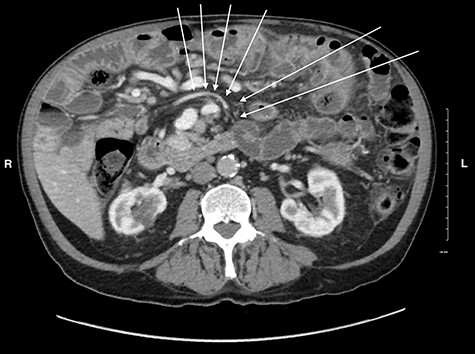

A 79-year-old male presented with 2 weeks of persistent abdominal pain. He did not report any nausea, vomiting or chills. Past medical history included aortic stenosis and type II diabetes, and no history of previous abdominal surgery. His abdomen was soft, non-distended, with mild generalized tenderness and an incidental umbilical hernia. Vitals signs were normal. His white blood cell count was 16.7 × 109/L. CT identified multiple distended and inflamed jejunoileal diverticula. There was no free fluid or gas (Fig. 1). The patient was admitted with small bowel diverticulitis and managed with bowel rest and intravenous antibiotics. He was discharged on post-admission Day 3.

CT scan of the abdomen and pelvis showing small bowel diverticula with inflammation and stranding consistent with uncomplicated diverticulitis.